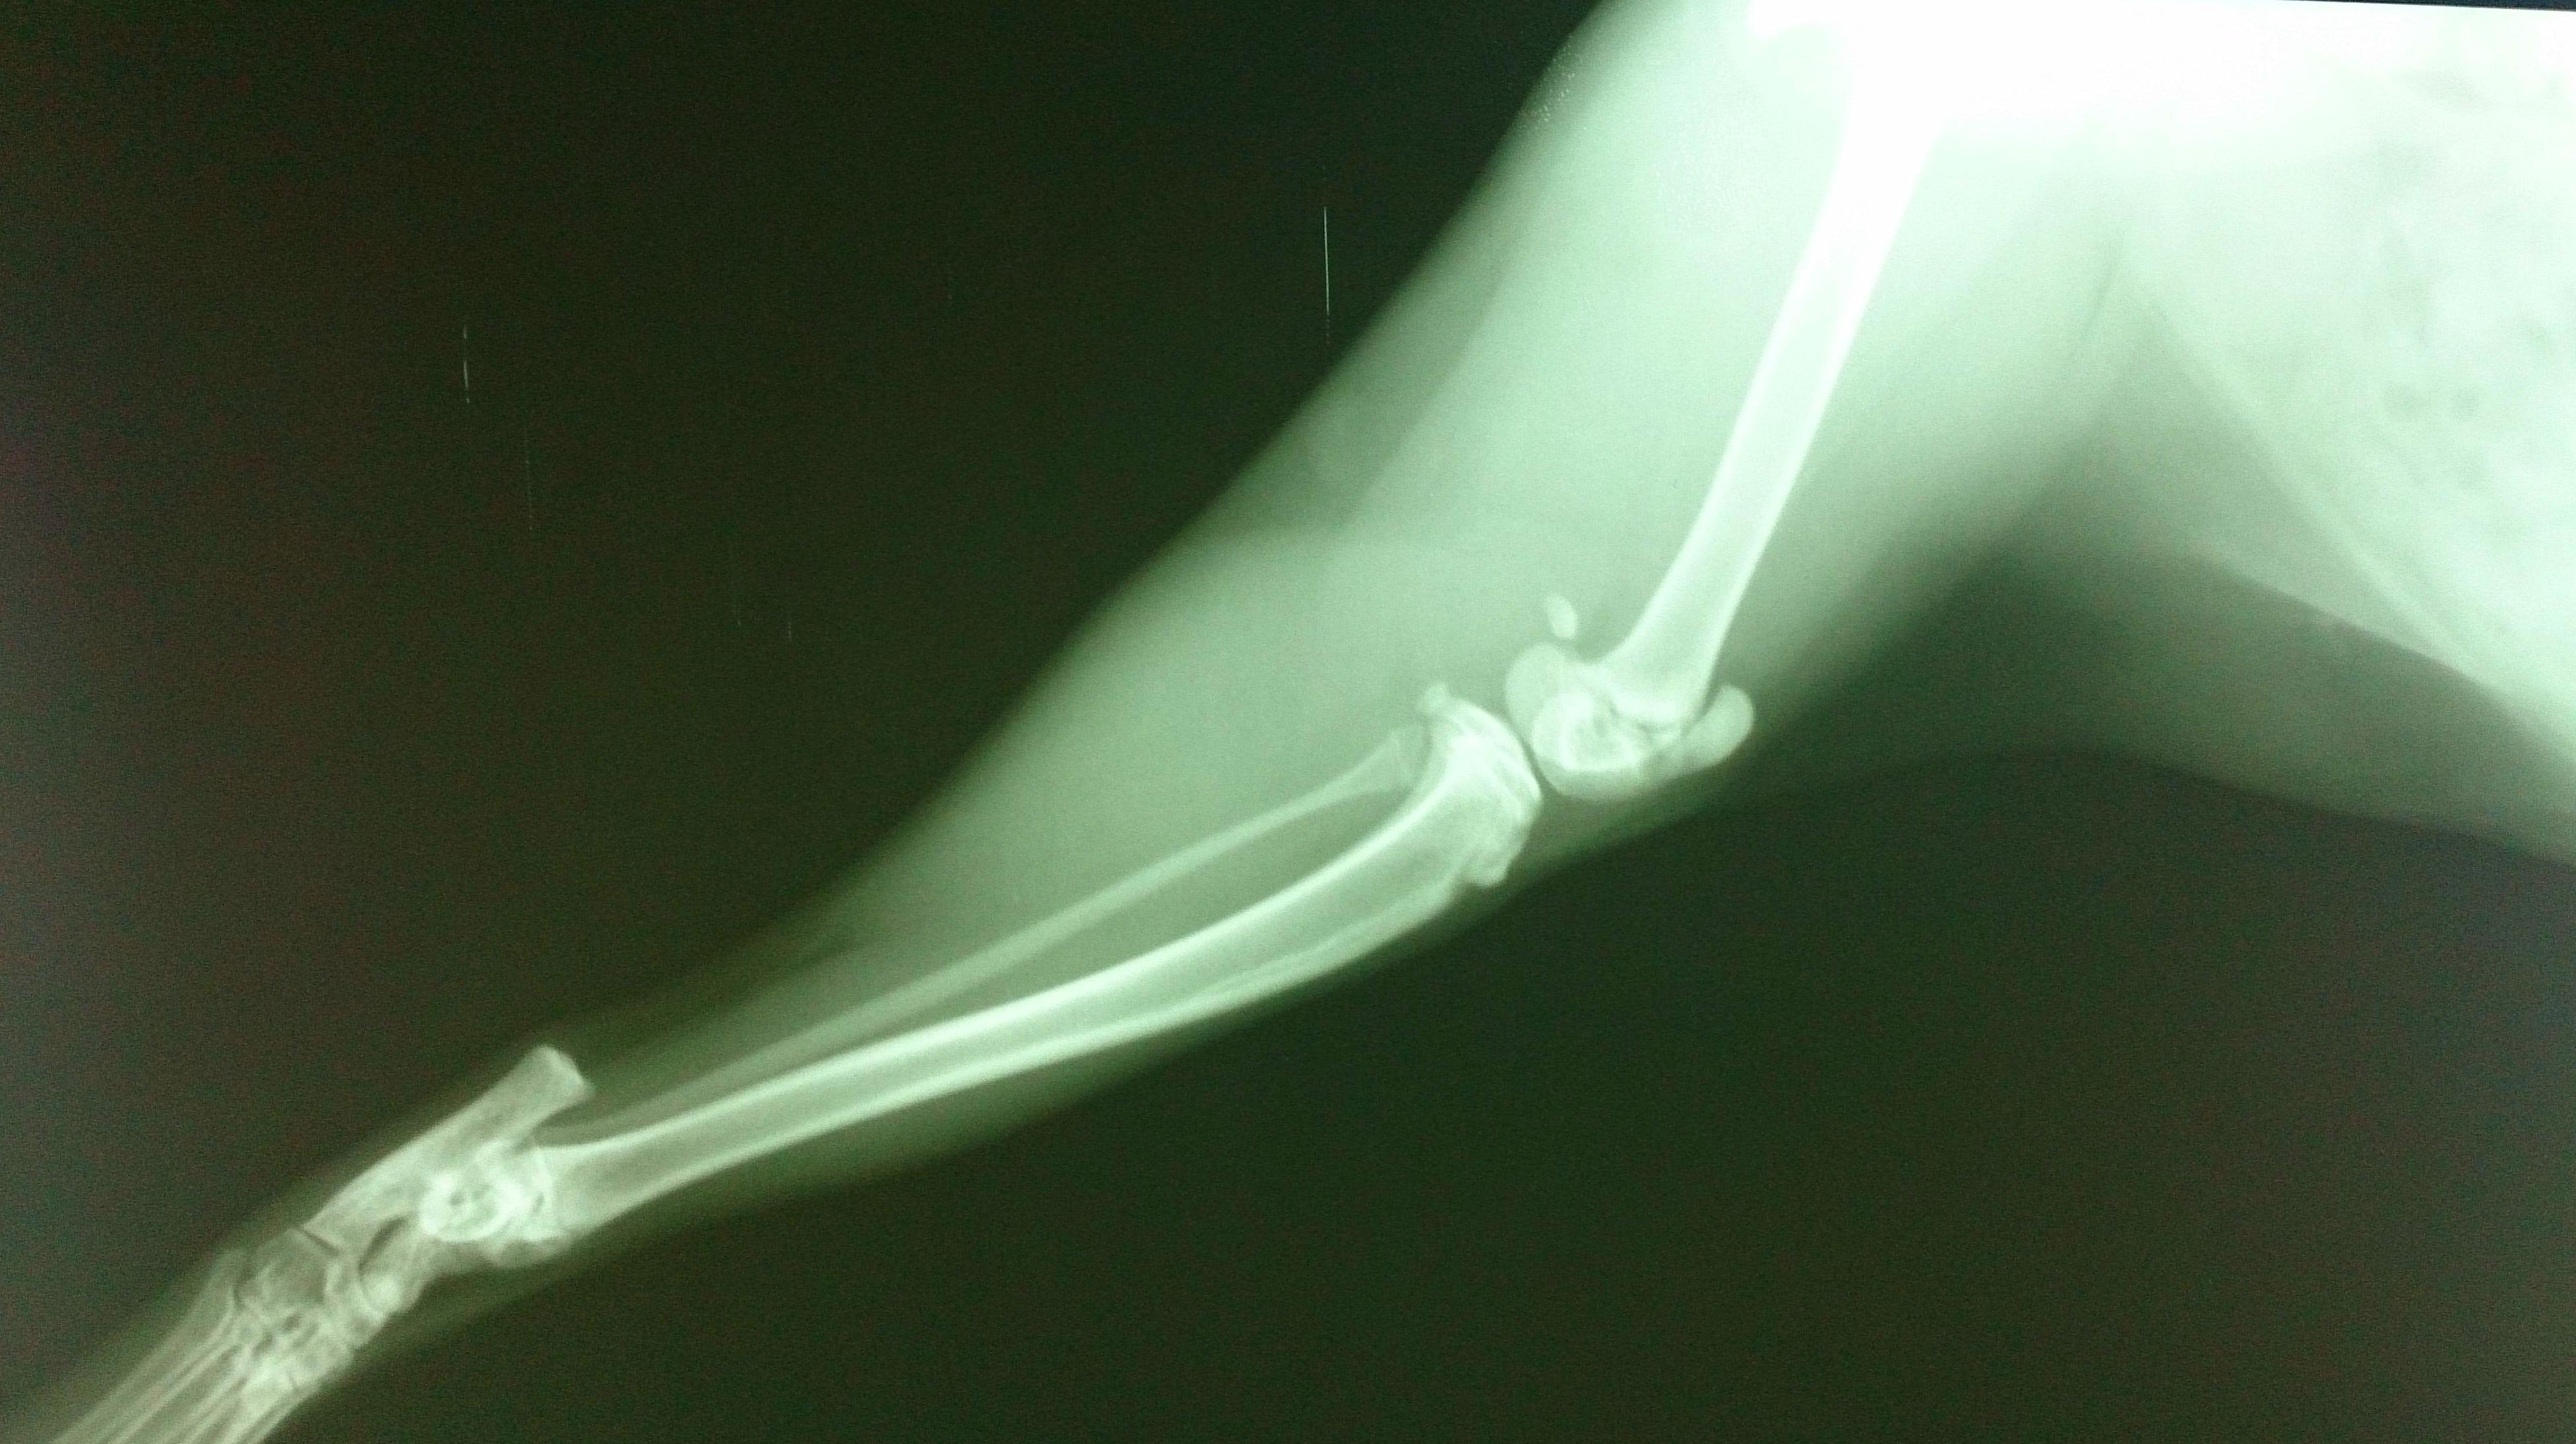

RADIOGRAFIA NORMAL EN UN GATO JOVEN,PROYECCIÓN LATEROLATERAL